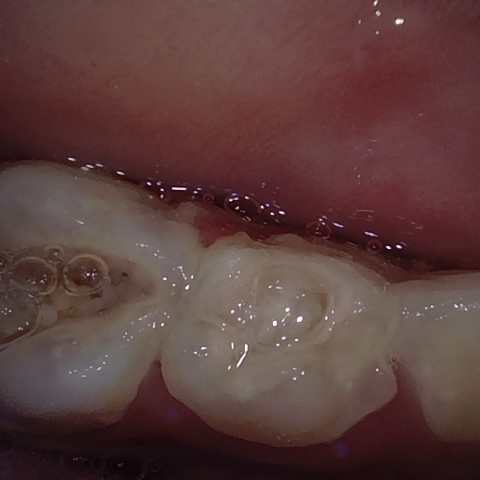

NHD25463

Annotated as "Good"